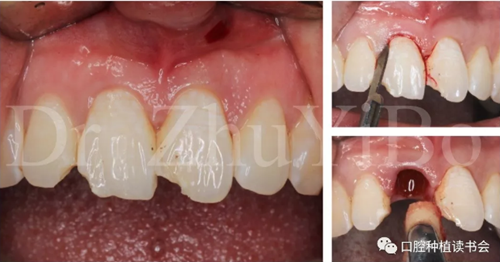

4.2.1微創(chuàng)拔出牙齒,挺出根尖(圖9)

圖9 斷裂牙根需用微創(chuàng)器械拔除

4.2.2 拔牙窩沖洗,定點,備洞(圖10)。

圖10 種植窩洞相對于天然牙長軸偏向腭側

4.2.3 植入Nobel active種植系統(tǒng) RP 13mm種植體,植入扭矩大于45Ncm,初期穩(wěn)定性良好(圖11、圖12))。

圖11 使用Nobel active手用植入扳手精確控制植入方向

圖12 種植體初期穩(wěn)定性良好,注意與唇側骨板間的間隙